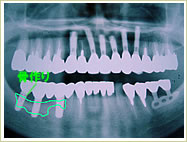

症例 54歳 男性 インプラント埋入数:11本 画像拡大

治療前 治療後